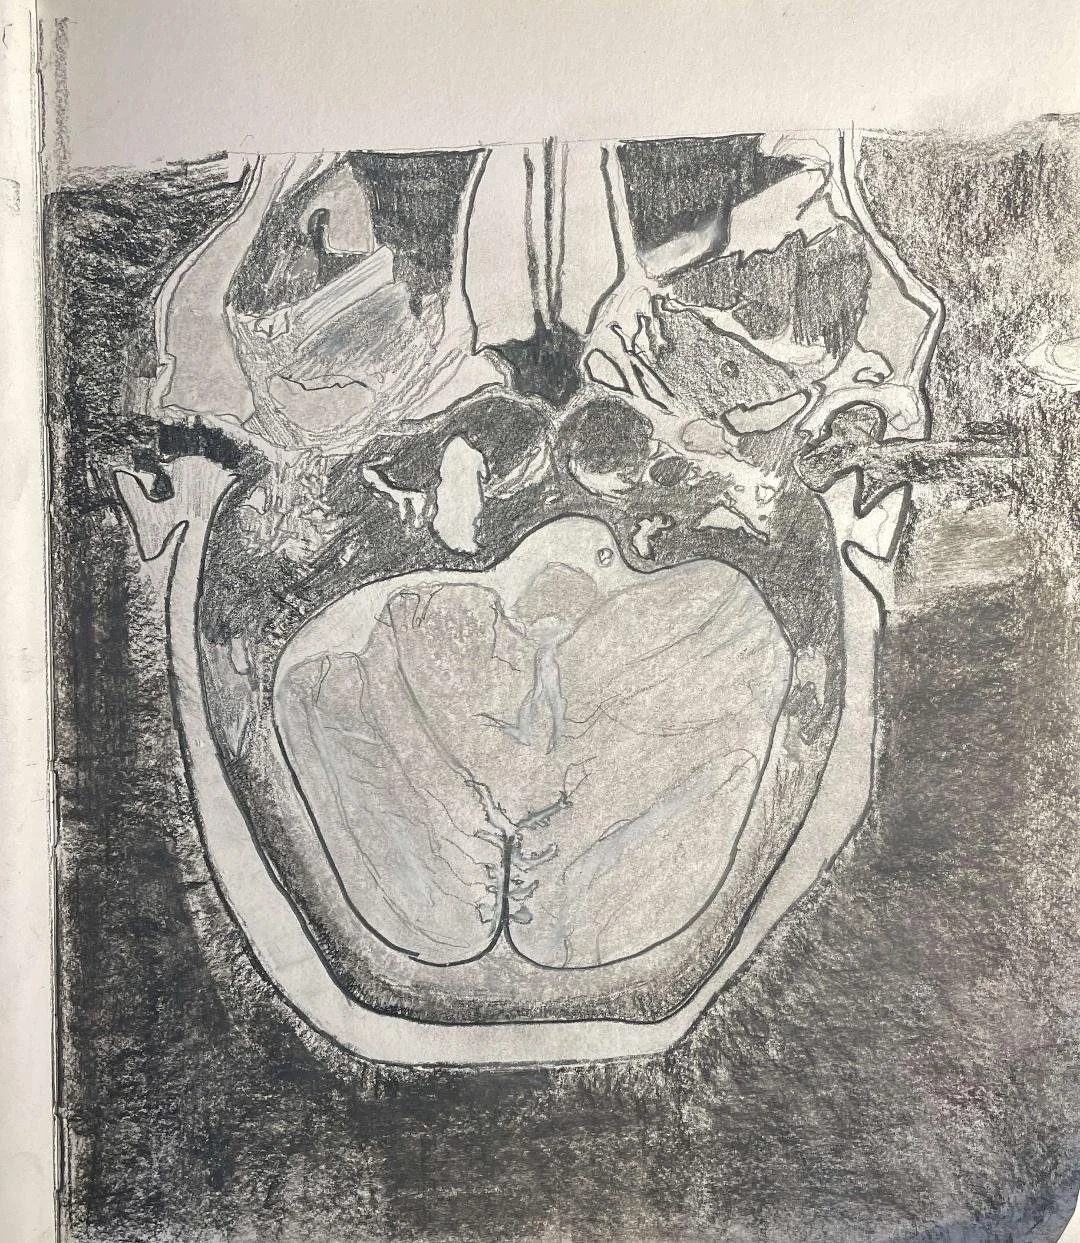

Telangiectatic osteosarcoma - skull

Chondrosarcoma

Myxofibrosarcoma: calvarial

Osteomyelitis of the ischiopubic synchondrosis

Tuberous sclerosis